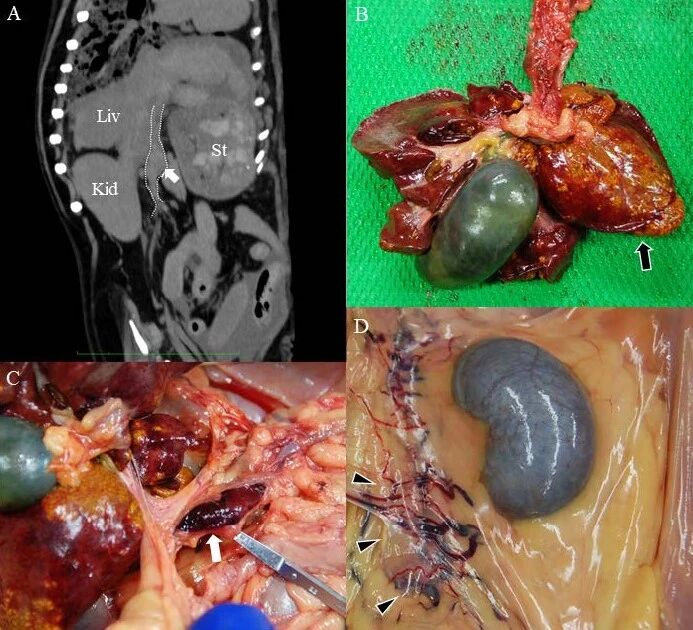

尸检和组织病理学检查结果包括梗阻性黄疸慢性肝炎和PVT(上图BC及下图)。

↑ 组织病理学发现。(A)肝脏:可见肝细胞慢性肝炎伴胆汁淤积(黑色三角),肝细胞的空泡变性,以及单核细胞浸润。(B)门静脉血栓形成:血栓主要由纤维蛋白、纤维化和色素组成,并与血管壁表现为纤维性黏连(黑色箭头)。